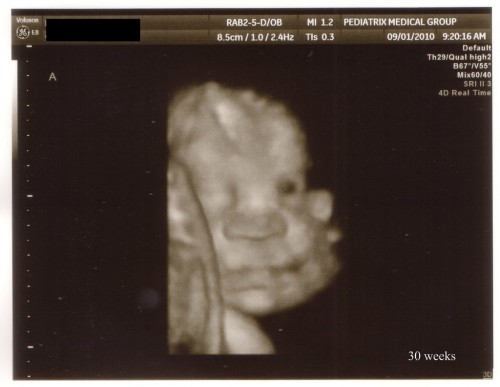

He actually cooperated enough at one point that the technician decided to grab the other transducer out and got a 4D picture for us! You can see part of Baby B (Ian) to the left of Baby A’s head. It will be interesting to see how much this picture actually looks like him when he’s born.

Baby A 4D